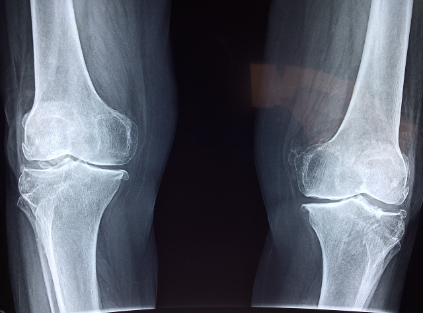

골관절염 및 관절 건강: 골관절염은 연골의 파괴를 특징으로 하는 흔한 퇴행성 관절 질환입니다. 일부 연구에서는 글루코사민 보충제가 골관절염 증상을 관리하고 질병의 진행을 늦추는 데 도움이 될 수 있다고 제안합니다. 그 아이디어는 글루코사민을 보충하면 신체에 연골 복구 및 합성을 위한 추가 구성 요소를 제공할 수 있다는 것입니다.

관절 건강은 개인이 불편함이나 통증 없이 자유롭게 움직이고 일상 활동을 수행할 수 있도록 하는 전반적인 웰빙의 중요한 측면입니다. 관절은 뼈 사이를 연결하는 역할을 하며 안정성을 제공하고 움직임을 원활하게 하는 데 중요한 역할을 합니다. 최적의 관절 건강을 유지하는 것은 이동성, 유연성 및 삶의 질에 직접적인 영향을 미치기 때문에 모든 연령대의 개인에게 필수적입니다. 여러 가지 요인이 관절 건강에 영향을 미치며 이를 이해하면 개인이 관절을 보호하기 위해 사전 조치를 취하는 데 도움이 될 수 있습니다.

글루코사민은 관절 건강 관리, 특히 골관절염과 관련된 잠재적 이점으로 인해 주로 관심의 대상이 되어 왔습니다. 골관절염은 연골이 파괴되어 통증, 뻣뻣함, 관절 기능 저하를 초래하는 일반적인 퇴행성 관절 질환입니다. 글루코사민은 신체에서 자연적으로 발생하는 화합물이며 관절을 완충시키는 결합 조직인 연골의 핵심 구성 요소입니다. 글루코사민을 건강 보조 식품으로 사용하는 이유는 신체에 연골 복구 및 유지 관리를 위한 추가 구성 요소를 제공하는 것입니다. 글루코사민이 주목받는 이유는 다음과 같습니다.

관절 건강 및 골관절염 관리: 연구에 따르면 글루코사민은 항염증 특성을 가지며 연골 보호 및 복구에 기여할 수 있다고 합니다. 일부 연구에 따르면 글루코사민 보충제를 복용하면 관절 통증 및 경직과 같은 골관절염 증상을 줄이는 데 도움이 될 수 있습니다.